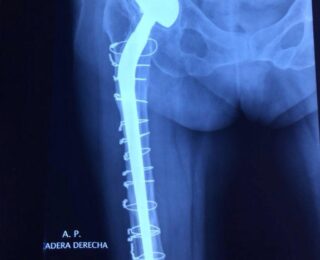

Femenino de 85 años de edad con prótesis bipolar de cadera, (figura 1 y 2) colocada en la Ciudad de México hace 22 años, estas prótesis funcionan de manera similar a una hemiprotesis, provocando destrucción y hundimiento en el Acetábulo.

Se realiza reconstrucción con Acetábulo cementado por las condiciones del paciente, el cual cursa actualmente sin dolor en cadera. (figura 3).